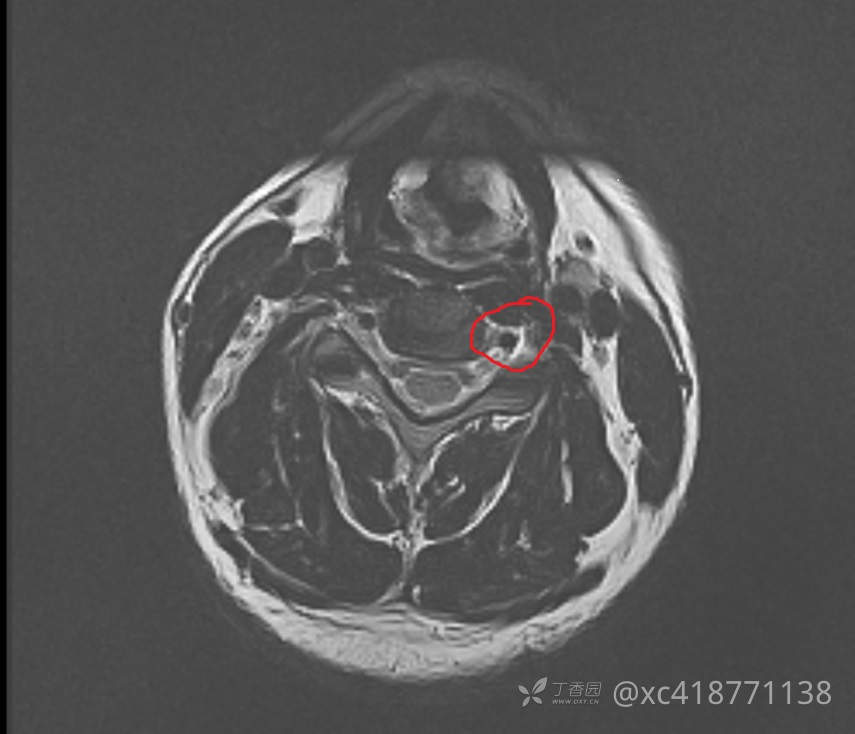

辅助检查:入院查心电图、胸片示正常。腹部+泌尿系B超示脂肪肝。双肾CT示:右肾小结石。附见:L5椎体I°滑脱,双侧椎弓峡部裂,隐裂。颈椎MRI示:2023-01-18 颈椎磁共振平扫(1.5T),颈椎退行性改变:骨质增生;黄韧带稍增厚。椎间盘变性伴C3/4-C6/7椎间盘不同程度膨、突出,双侧神经根受压,椎管稍狭窄,伴颈髓略受压,C4-6左侧神经根T2WI信号稍增高,结合临床。2023-01-18 左肩关节磁共振平扫(1.5),1、左肱骨头关节面下少许骨损伤。2、左侧肩袖前上份损伤,冈上肌、肩胛下肌腱损伤,伴肩袖周围渗出。3、左肩关节肱二头肌长头盂唇复合体(SLAP)损伤可能,结合临床。4、左肩关节下关节囊增厚,考虑慢性损伤可能。5、左三角肌下滑囊及喙突下囊少许积液。6、左肩锁关节炎?。2023-01-17 胸部正侧位,两肺、心膈未见异常。

临床诊断: 疾病诊断:1.颈部脊髓损伤(左侧C4)2.左臂丛神经损伤3.左肩袖损伤4.左肾结石。功能诊断:1.左上肢运动障碍2.颈部、左肩部及上肢疼痛3.日常生活大部分自理